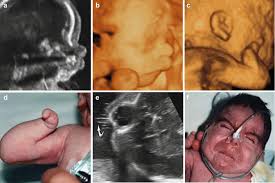

If the 2D ultrasound does not demonstrate two nasal bones then 3D ultasound may be useful. An ultrasound scan There is no risk to the baby from either of these procedures. October 15 2018 Shane Dale According to the National Down Syndrome Society NDSS during the normal fertilization of a womans egg by a mans sperm the resulting nucleus of each cell in a fetus contains 23 pairs of chromosomes half of which are inherited from each parent.

For this reason 3D ultrasound reconstruction of the nasal bone and other facial bones is useful. At this stage the babys legs arms fingers and toes should be fully formed. Mothers should not be encouraged to have an ultrasound called a.

Of the many defects 3D 4D ultrasound has been useful in evaluating the skeletal and cardiovascular systems in fetuses with this condition. But keeping tabs on your babys growth can be a good thing and knowledge is power. By combining the results of the two parts of the test it is possible to identify if a pregnant woman is at increased risk of having a baby with Down syndrome.

A normal heart rate for a baby ranges from 120 to 160 beats per minute. By itself the test does not tell. These include increased nuchal translucency short femurs and abnormalities of the heart bowel and kidneys.